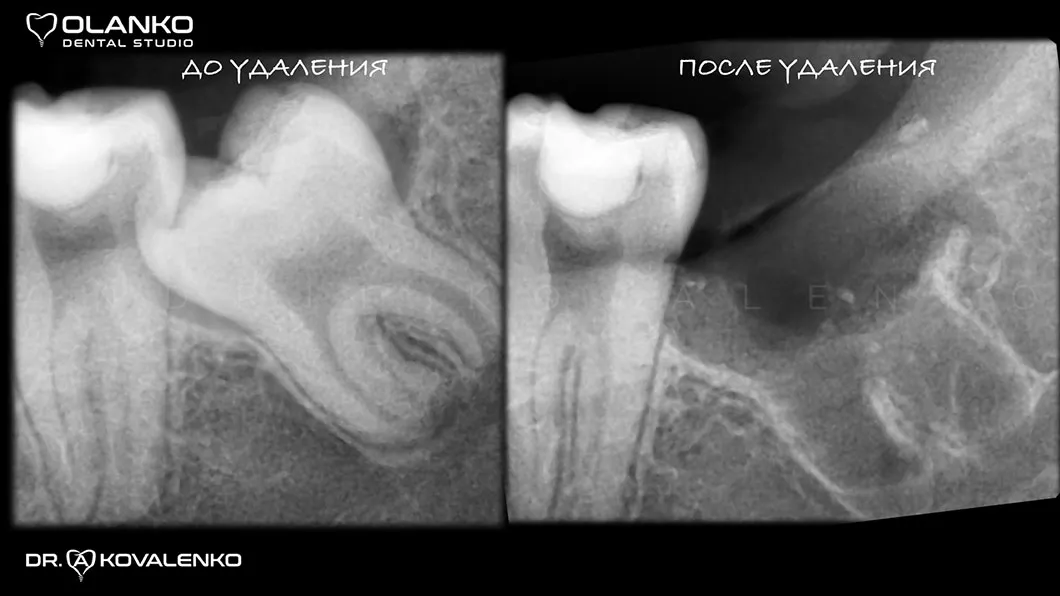

Фото рентген до и после удаления ретенированного зуба мудрости

Фото рентген до и после удаления зуба мудрости Оланко Бровары Киев